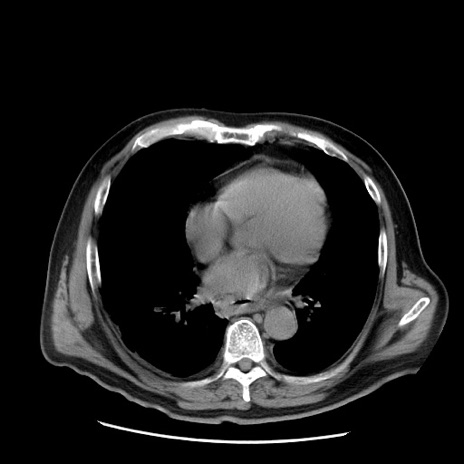

症例20(横断像)

【症例】 60歳代男性

【主訴】 腹部膨満、嘔吐

【現病歴】5日前頃より倦怠感を認め食事量減少し4日前の朝嘔吐、食事摂取困難となった。 3日前近医受診し点滴施行され整腸剤などを処方された。 当日他院を受診し、腹部膨満著明、炎症反応の上昇(CRP10.8、WBC11200)あり、紹介受診となる。

【身体所見】 意識JCS1 受け答えがはっきりしないBP 111/57mHg、 P 67bpm、、BT35.2°C、SpO2 97%(RA)、 腹部:膨隆、打診で鼓音あり、全体的に圧痛有り、腸蠕動音(-)、反跳痛ははっきりせず。

【データ】WBC 11400、CRP 14.20